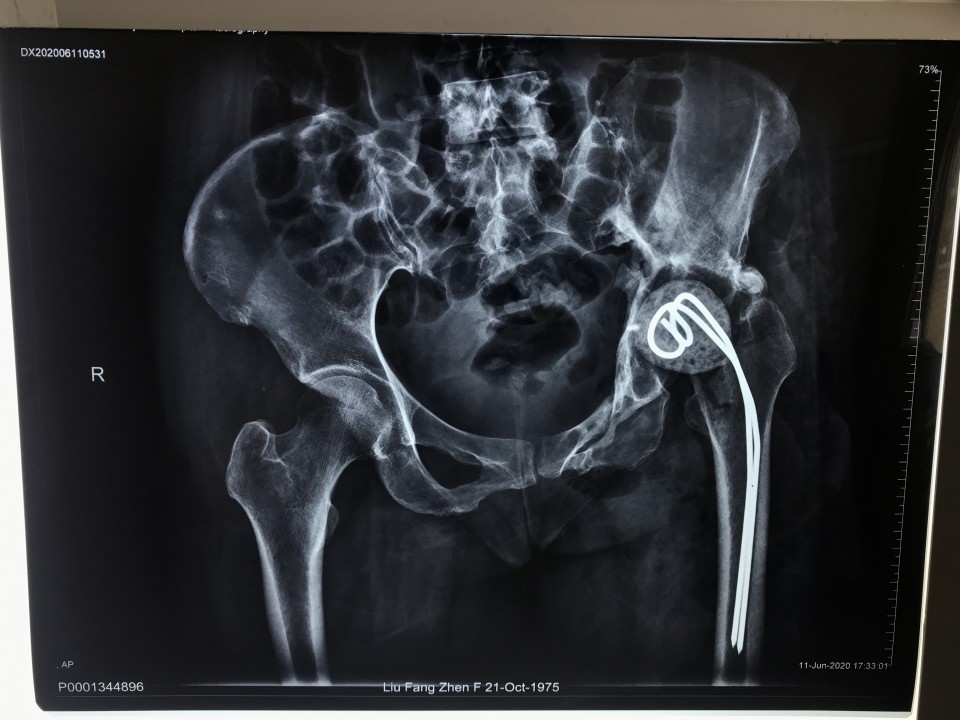

一位44岁女性患者因“左侧骨盆骨折术后疼痛伴渗液8年”入院。患者8年前因左侧骨盆骨折请上海专家行手术治疗,术后恢复不佳,髋关节感染,当地医生将部分钢板取出,残留的钢板因风险极大未予以处理。由于手术不彻底,伤口继续流脓,股骨头坏死,关节疼痛严重。因为手术风险极大,失败率高,多家医院拒收,患者慕名来到我院关节与显微修复外科胡孔足主任专家门诊,胡主任综合考虑各方因素以及现阶段我院的诊疗技术,将患者收治入院予以手术。术前结合患者病史,体检及辅助检查,反复讨论,制定了精细的手术方案,于6月10日,成功行一期手术,取出感染发炎的钢板,植入抗生素占位器。因为钢板和血管神经紧紧粘连在一起,稍有不注意就可能导致大出血,瘫痪、心跳骤停等严重后果。术后培养提示为MRSA,经过两个月规范抗感染治疗,培养提示阴性,未见细菌,感染消失。8月12日,胡主任顺利完成二期手术,“左侧全髋关节置换术”,目前手术后4天,患者已经能够扶拐下地行走,恢复良好,不久将康复出院。